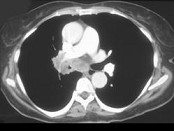

- 单项选择题男,56岁, 咳嗽,咯血1月余, 有吸烟史30余年,结合CT检查, 最可能的诊断是 ( )

E、中央型肺癌